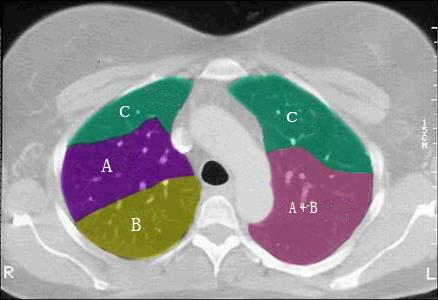

结合肺段模式心室层面(如图),选出右肺上叶的组成 ( )A.AB.A+BC.A+B+CD.A+B+C+DE.A+B+C+D+E

问题 结合肺段模式心室层面(如图),选出右肺上叶的组成 ( )

选项 A.A B.A+B C.A+B+C D.A+B+C+D E.A+B+C+D+E

答案 C